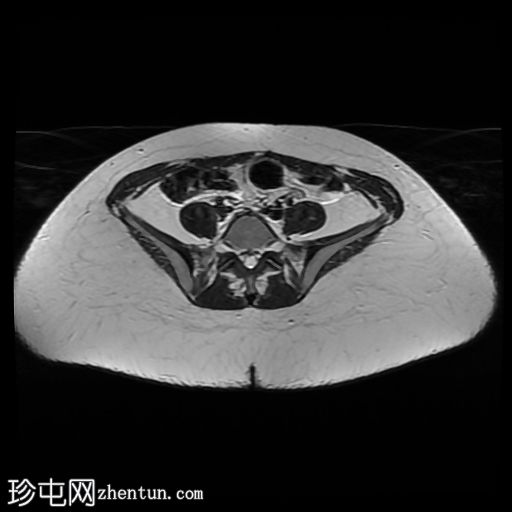

轴位(沿子宫矢状轴的SFOV)T2

轴位

偶然发现子宫纵隔,子宫角间夹角为51度,纵隔长度为19mm。

子宫底部可见少量壁内及浆膜下肌瘤。